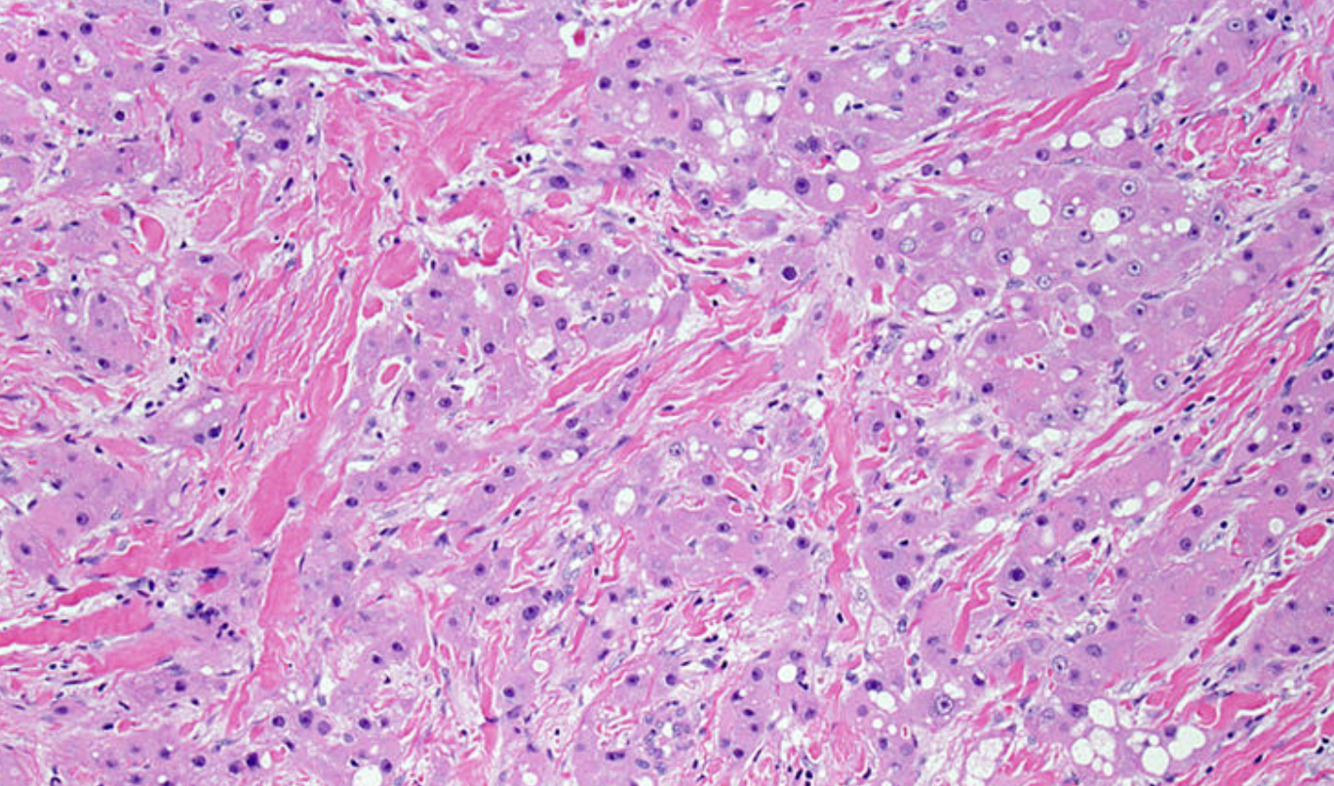

descending colon polyp 44F

Dx:

Features in image

IHC:

A

Dx: Schwann cell hamartoma

Image demonstrates bland spindle cell proliferation with elongated nuclei and dense eosinophilic cytoplasm, which is consistent with Schwann cell proliferation.

IHC: S100 (+) EMA/DOG1/CD43/SMA (-)